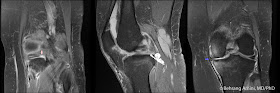

The vast majority of POEMS syndrome patients have radiographic evidence of bone lesions at presentation. Slightly less than half of these lesions are purely sclerotic (well-defined or fluffy), approximately half are mixed sclerotic and lytic, and a small number (2%) are purely lytic bone lesions, which tend to have scelrotic margins giving them a

unique ring-like appearance. More than half of patients with bone lesions had more than one lesion.

Resnick has described a pattern of bony proliferation that is pathognomonic for POEMS syndrome: irregular and spiculated bone contours at areas of tendinous and ligamentous attachment, posterior elements of the spine (facet joints, laminae, transverse processes, and costovertebral articulations).

The images above are from a patient with POEMS syndrome. We see sclerotic lesions in the humerus, pelvis, and proximal femur, some of which have the typical ring-like appearance (e.g., the left intertrochanteric region). Looking through our 20 or so cases of POEMS here, I wasn't able to find any with the pathognomonic proliferative changes described by Resnick, so a look at the original paper is worthwhile to get familiar with this appearance.